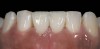

Fig. 5 The postoperative situation. Clinical work and photographs by Dr. Markus Blatz, dental technology by Cusp Dental Laboratory, Malden, MA.

Figure 5

The clinical application of this protocol is illustrated in a patient situation where laminate veneers were placed on four maxillary incisors to replace lost tooth structure and restore function and esthetics. The failing restorations were removed, followed by a conservative veneer preparation (Figure 1 and Figure 2). The bonding surfaces of the feldspathic porcelain veneers were acid-etched with hydrofluoric acid for 2 minutes (Figure 3) and thoroughly rinsed. Then a silane coupling agent was applied (Figure 4). Figure 5 demonstrates the situation after bonding the veneers to the teeth with a composite resin luting agent.